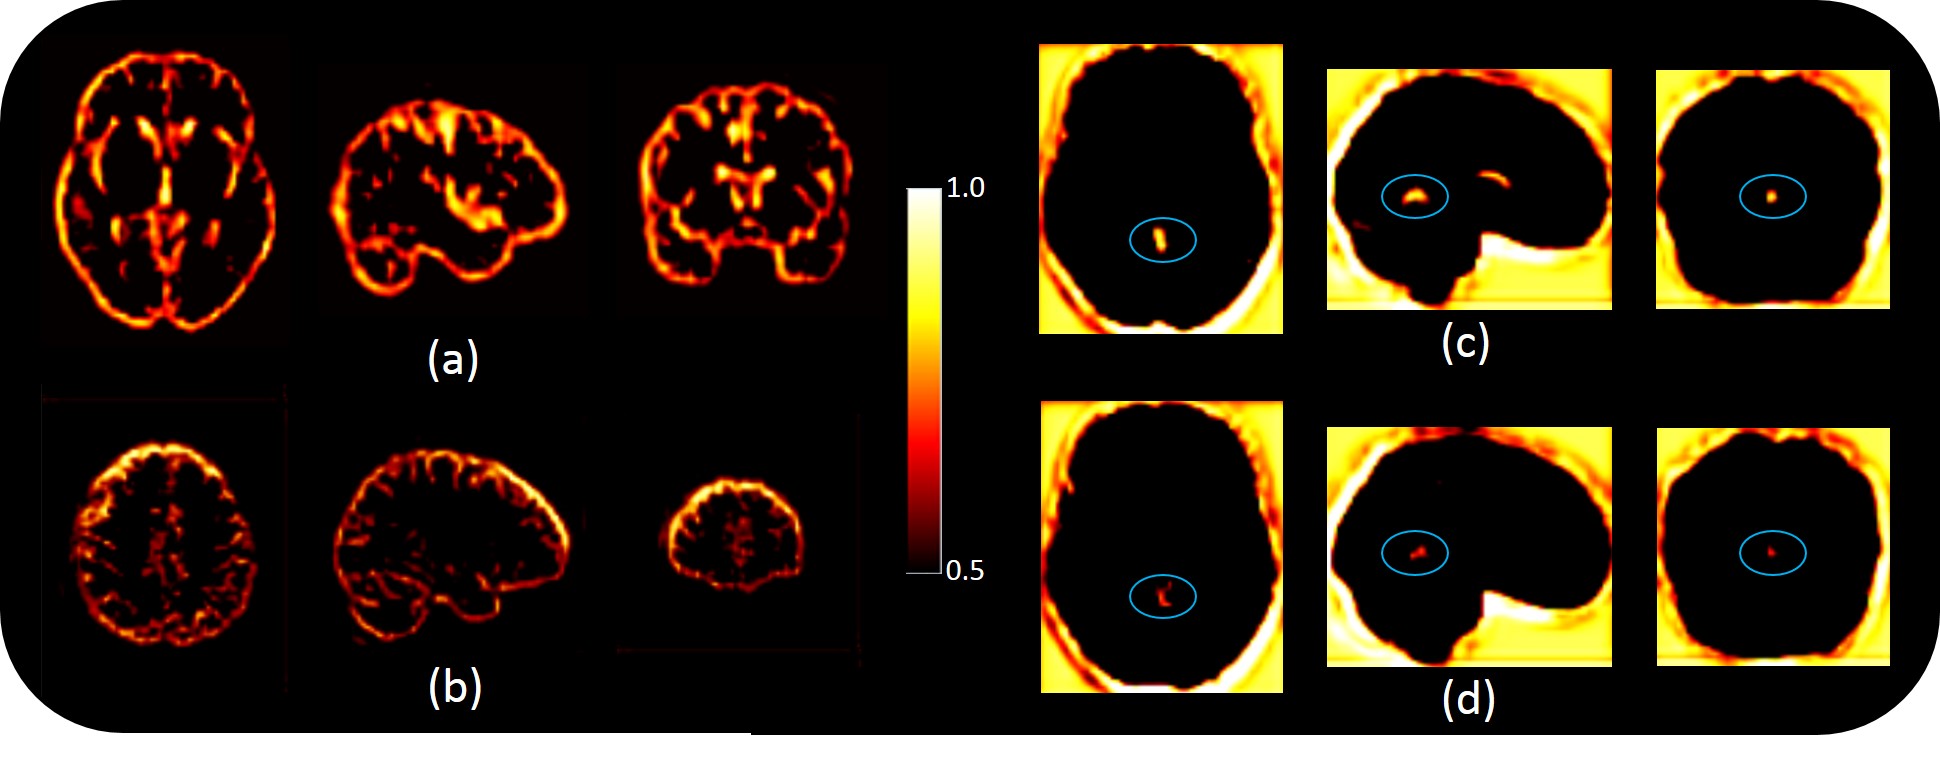

Refer to caption

Figure 10: Visualization of internal features from global module: (a) Feature that detects the overall uptake pattern covering regions most commonly associated with AD (cortex, subcortex, ventricles, etc.) (b) Feature that perceives relatively significant importance of superior frontal gyrus in AD (c) & (d) Feature that detects the vermis region of the cerebellum (associated with early stages of AD) validated by intensity differences between a CN and an AD sample respectively.

Although many of the features did not lend themselves readily to human interpretability, we were able identify some features from the global module (Ggsubscript𝐺𝑔G_{g}) of the GLA-GAN that were relevant to this particular task. Some of the commonly used biomarkers for Alzheimer’s include cortical and subcortical atrophy and dilation of ventricles. One of the features characterized these specific brain regions as shown in Figure 10 (a). Furthermore, several neuroimaging studies have identified specific brain regions most prominently affected by the disease [46]. The feature depicted in Figure 10 (b) highlights the relative significance of superior frontal gyrus region. Metabolic changes in this particular region has been associated with cognitive decline [47]. In addition to these overall features, we identified a feature that emphasized the potential contribution of a specific brain region for AD diagnosis. Figures 10 (c) and (d) display the same feature that illustrates the importance of vermis region of the cerebellum with intensity differences between the normal and AD subjects respectively. This particular region has been implicated to be affected in the early stages of the disease [48] which could be crucial for timely diagnosis.

It was very encouraging to detect internal features from the global module that exhibited strong connotations characteristic of Alzheimer’s disease. Unfortunately, as the individual subnetworks of the local generator module are trained independently, the concatenated versions of the local features were not easy to decipher. Subsequently, we found it difficult to identify feature maps from the end-layer that could be interpreted in terms of contributions associated with global and local components.